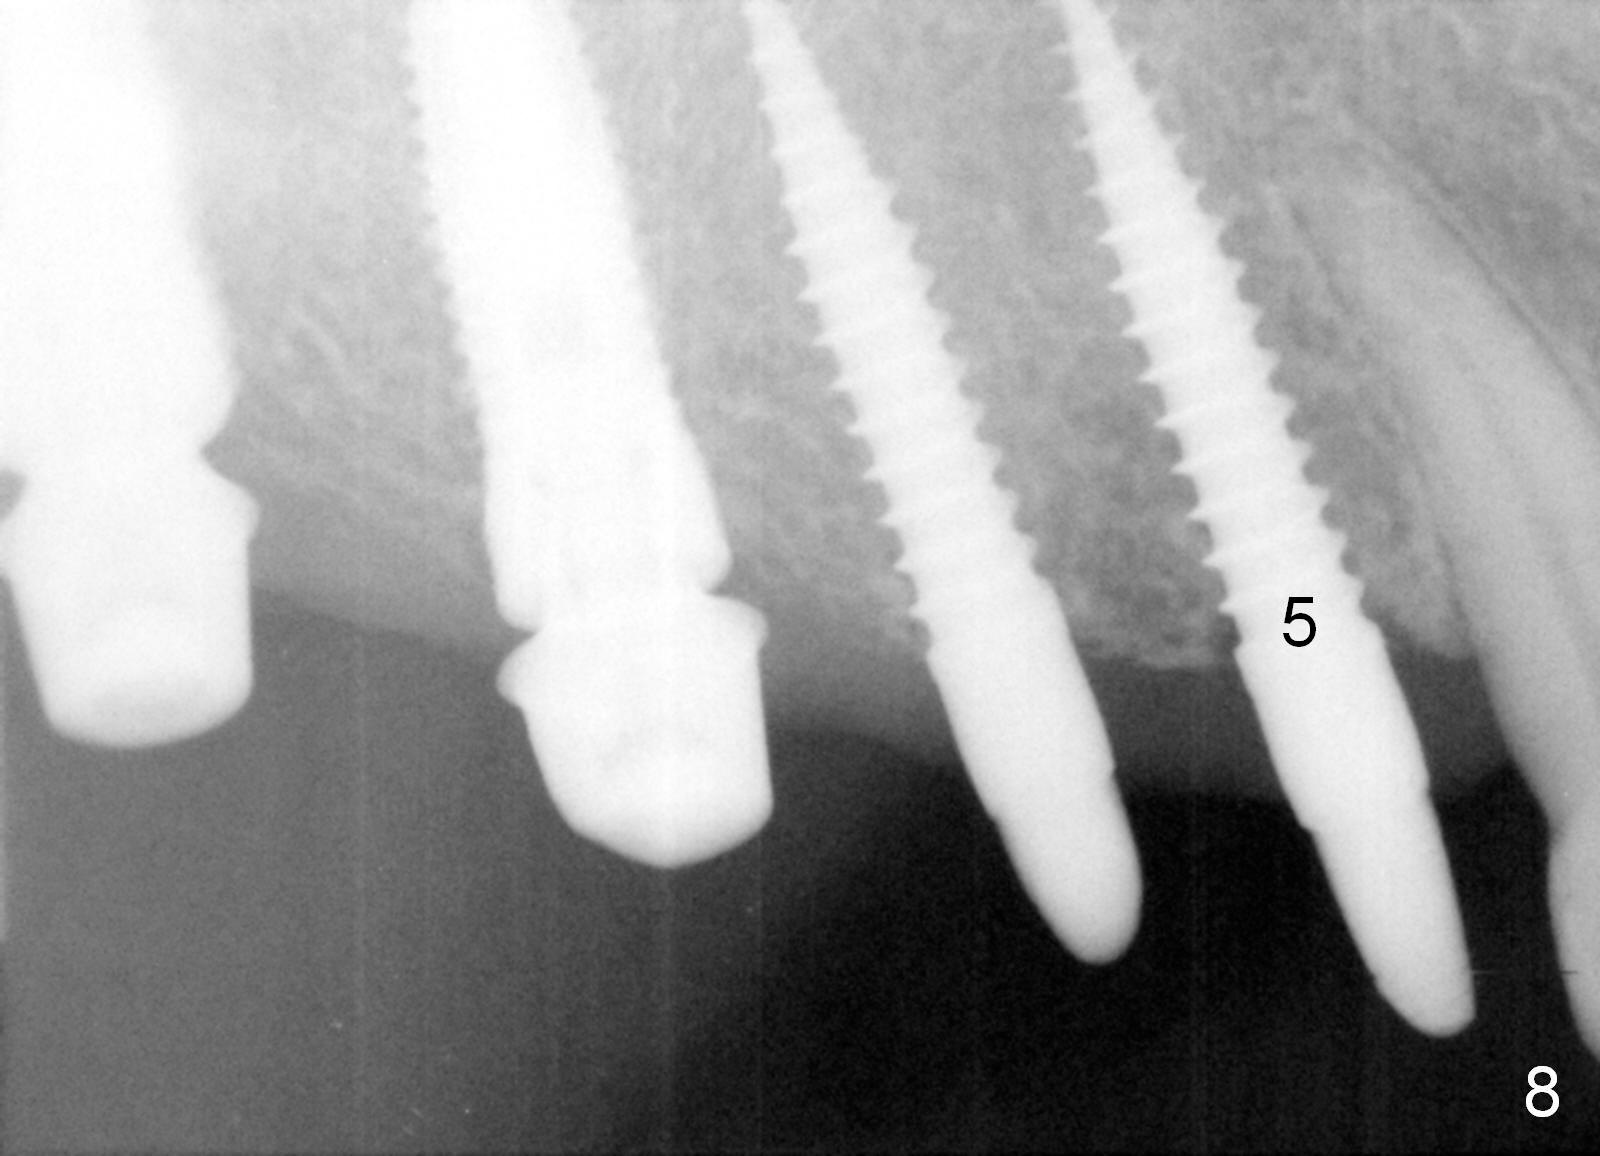

Osteotomy in the upper posteriors starts through a surgical stent for 12 mm. After incision, each osteotomy is examined, adjusted and extended 2 mm shy of intended (Fig.1,2). It appears that the trajectories at #4,5 are off (Fig.2). After re-adjustment, the trajectories are acceptable (Fig.3 (red dashed line; part of the root of the tooth #6)). Four implants are placed basically in accordance with the plan: 5.9x10 mm at #2, 5x14 at 3, and 3x14 mm 1-piece at 4 and 5 (Fig.4,5). Fig.6 shows the narrow ridge at #4 and 5 after implant placement. Although abutments are placed at #2 and 3, an immediate provisional bridge cannot be fabricated because of lack of enough clearance (supraeruption of the opposing dentition).

Provisional bridge is fabricated after wound healing. Four months postop, there is minimal bone resorption at the site of #5 (Fig.7,8). Single-unit crowns are fabricated.